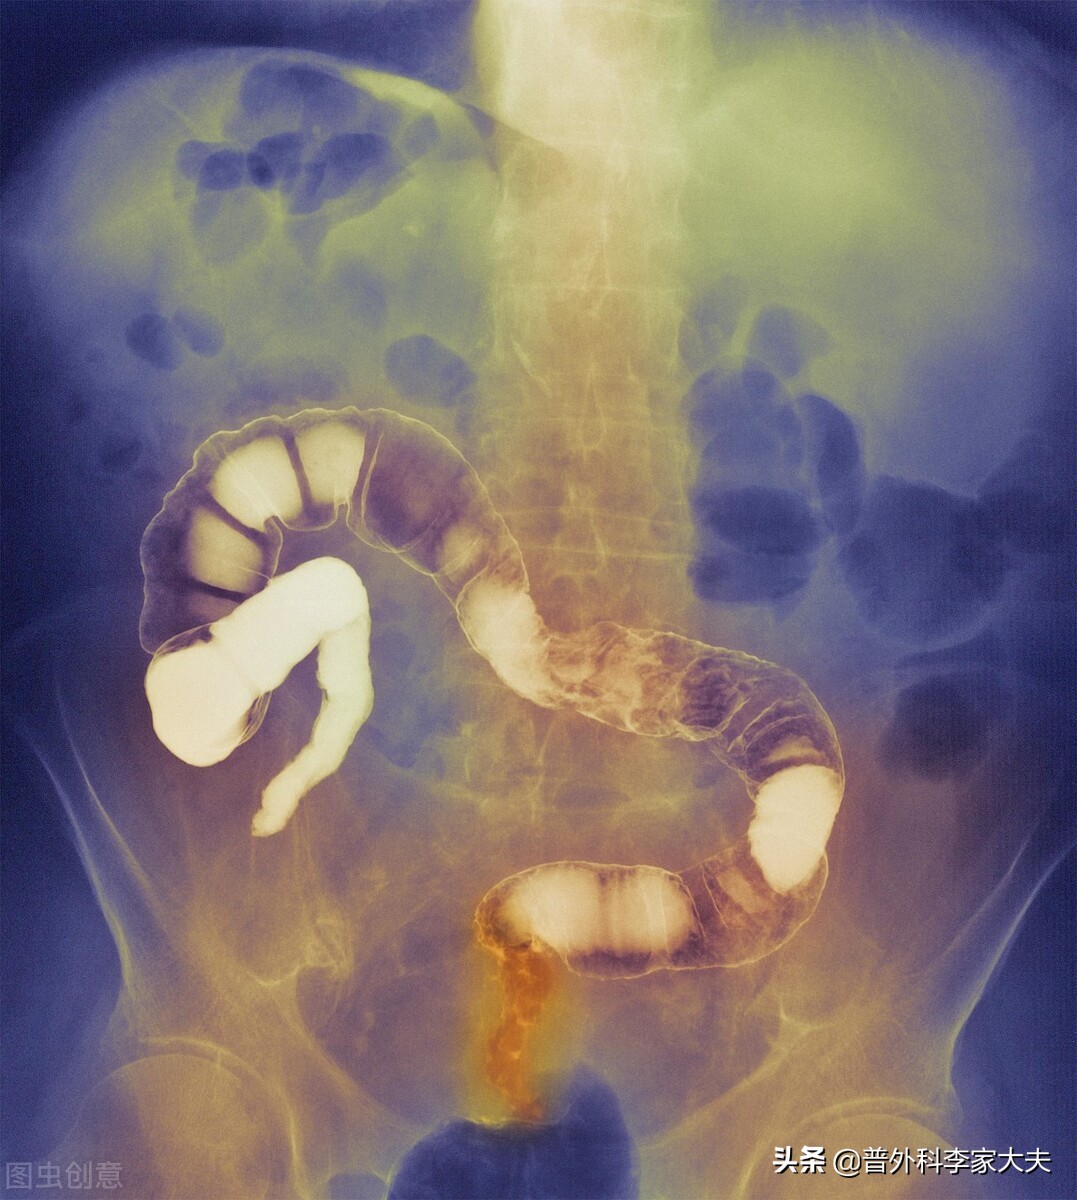

直肠癌的术后辅助放疗的适应症,经过大量临床经验总结,目前已形成了规范,并且也写入各大结直肠癌的诊疗指南中,具体适应症选择是:适用术前未经放疗,且术后病理提示局部复发风险高的情况,如环周切缘阳性、盆侧壁淋巴结转移、低分化腺癌、伴脉管瘤栓等。

患者的直肠癌大小为3.5cm×3.8cm,从我的临床经验考虑,直肠癌长到这样大的患者,他的直肠癌T分期估计应该是T3或T4分期。再加上患者术后发现有淋巴结转移1/12,我从最理想的情况分析,患者还没有发生远处转移,则患者的直肠癌病理分期应该是T3N1M0或T4N1M0的患者,也就是说患者的直肠癌术后病理分期就是ⅢB直肠癌。而这种类型的直肠癌患者,正是上面介绍的直肠癌术后放疗的适应症患者了。因此,从提高患者术后直肠癌疗效及安全的角度,患者是应该进行直肠癌的术后放疗的。